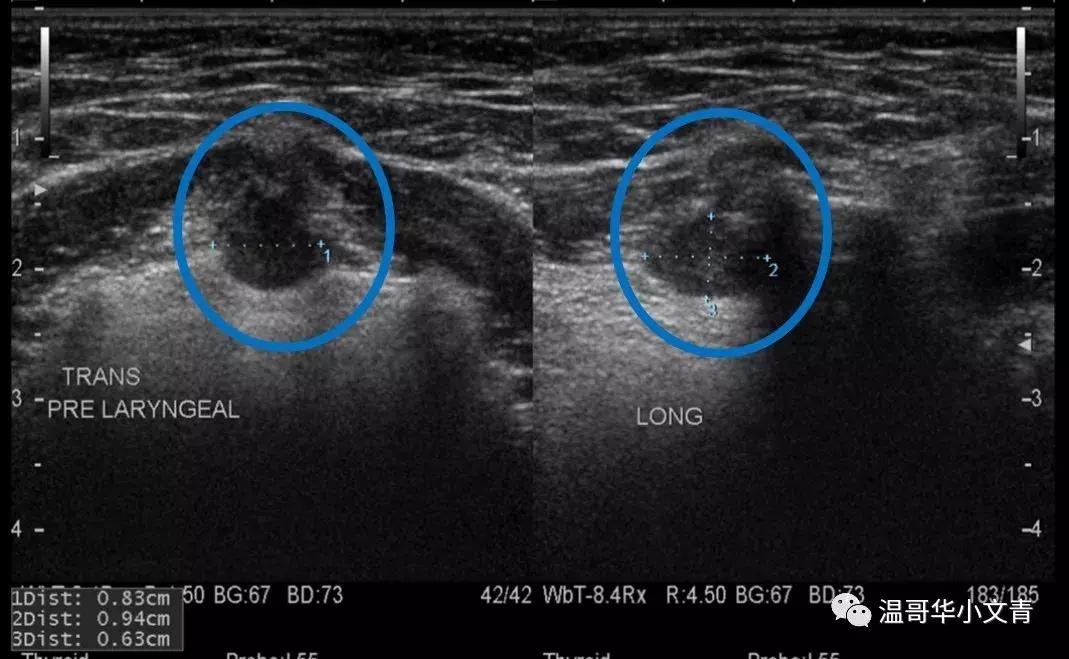

第一个图是一个术前发现的喉前可疑淋巴结,淋巴结长径是9毫米。这个淋巴结在彩超上看起来比较圆,而且边界很不规则,非常可疑,术后的病理显示这个淋巴结里的转移灶是4毫米。